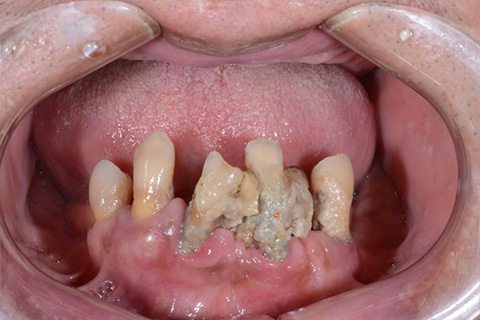

症例2

歯がグラグラで噛めない。骨が少なくてインプラントできない。という主訴でご来院頂いた患者様に対して「特殊プラスティック義歯」を使用した入れ歯の症例

術前

入れ歯での治療後